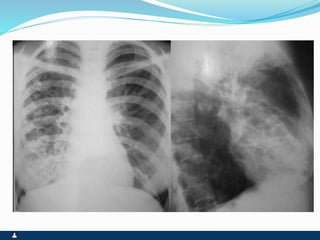

ATELECTASIA

ATELECTASIA ENFISEMA LOCALIZADO

 OBSTRUÇÃO BRONQUICA

COMPLETA

 RETRAÇÃO TORÁCICA OU

INTERCOSTAL

 DESVIO HOMOLATERAL DO

MEDIASTINO ( TRAQUÉIA)

 EXPANSIBILIDADE REDUZIDA

 FTV AUSENTE

 MACICEZ LOCALIZADA

 MV AUSENTE

 RONCOS OU SIBILOS

LOCALIZADOS

 ATRITO PLEURAL EVENTUAL